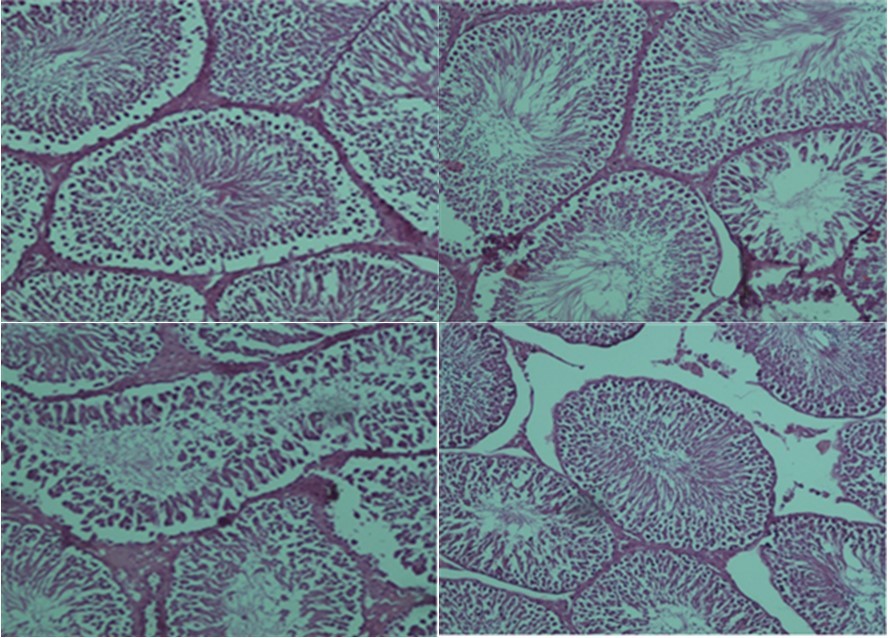

The results of the histopathological examination for each group are displayed in Figure 1, Figure 2. The presence of uniform seminiferous tubular morphology and there was normal testicular structure seen in the control and ozone/oxygen groups. In torsion/detorsion group, there was a severe distortion of tubules and a significant decrease in the diameter of the seminiferous tubular. Administration of ozone/oxygen protected the seminiferous tubular from damage after torsion/detorsion.

Figure 2.Light microscope observations of H&E stained sections (×100). (A) positive control group: normal testicular architecture was seen. (B) Health group+ ozone/oxygen (30µg/ml). (C) torsion/detorsion. (D) torsion/detorsion + ozone/oxygen (30 µg/ml) therapy group.